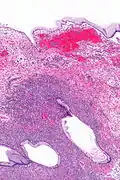

| Micrograph showing a mucinous cystadenoma of the ovary. H&E stain. | |

Mucinous cystadenoma is a benign cystic tumor lined by a mucinous epithelium. It is a type of cystic adenoma (cystadenoma).